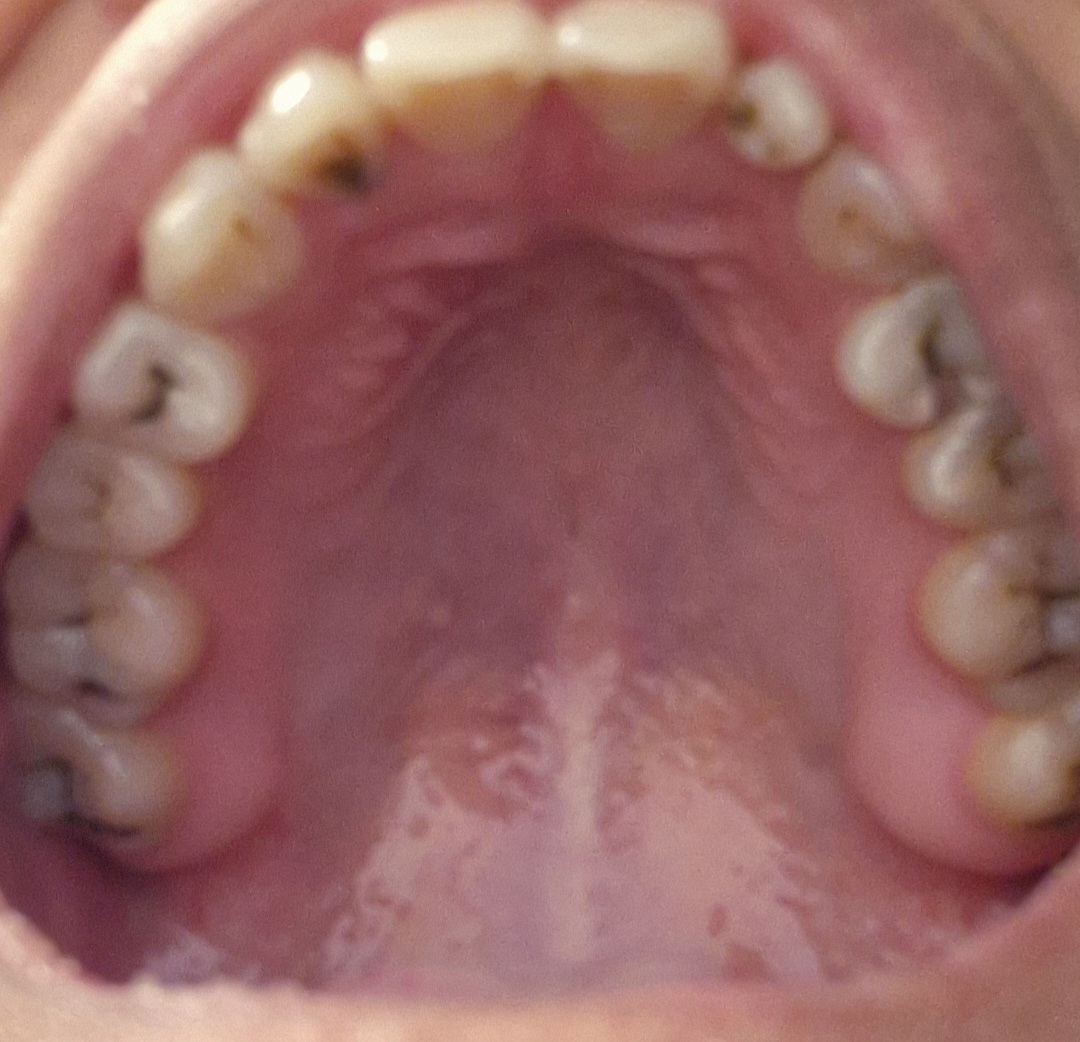

Hiện trạng răng của tôi như này liệu có điều trị khỏi được không?

Em cần điều trị sớm và hàn răng, tránh trường hợp để lâu hỏng tủy răng

Và phải thay răng mới

Chữa vẫn khỏi đc nhưng khá tốn tiền em nhé